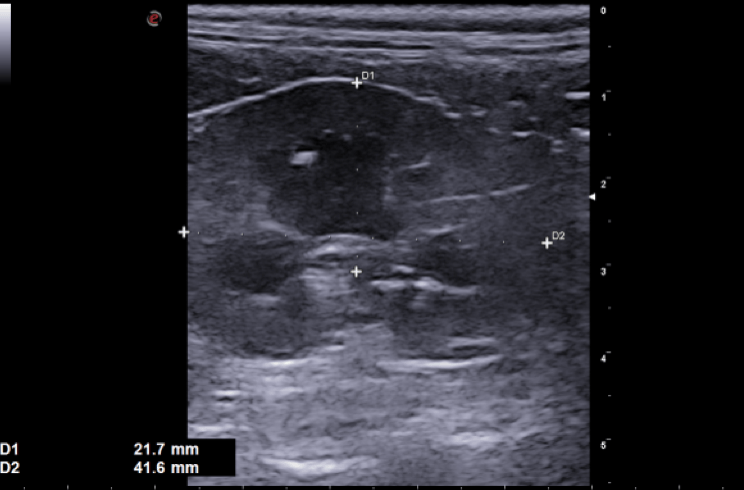

Tra i servizi che l’Ospedale Veterinario Città di Conegliano fornisce, non mancano quelli di diagnostica per immagini:

ecografia, radiologia digitale, TC.

Gli specialisti Roberto De Pellegrin e Riccardo Pelizzon, in particolare, si occupano degli esami ecografici, ecocardiografici, tomografici per l'acquisizione di immagini del corpo del paziente attraverso l'esposizione a ultrasuoni o a raggi X.

Si tratta di esami non invasivi né dolorosi, che possono essere eseguiti molto rapidamente.